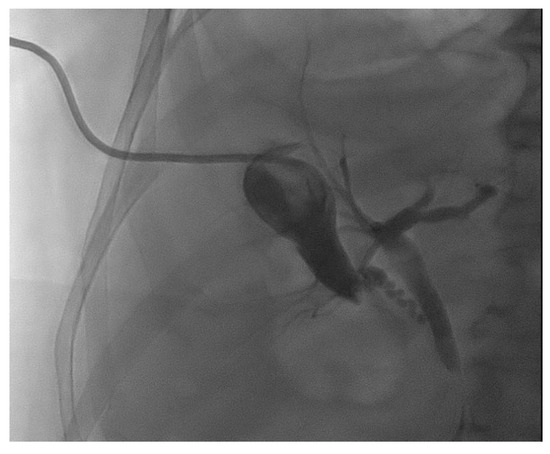

7. EUS–Gallbladder Drainage as a Rescue Strategy in Malignant Biliary Obstruction

- Itoi, T.; Binmoeller, K.; Itokawa, F.; Umeda, J.; Tanaka, R. Endoscopic ultrasonography-guided cholecystogastrostomy using a lumen-apposing metal stent as an alternative to extrahepatic bile duct drainage in pancreatic cancer with duodenal invasion. Dig. Endosc. 2013, 25 (Suppl. S2), 137–141. [Google Scholar] [CrossRef]

- Imai, H.; Kitano, M.; Omoto, S.; Kadosaka, K.; Kamata, K.; Miyata, T.; Yamao, K.; Sakamoto, H.; Harwani, Y.; Kudo, M. EUS-guided gallbladder drainage for rescue treatment of malignant distal biliary obstruction after unsuccessful ERCP. Gastrointest. Endosc. 2016, 84, 147–151. [Google Scholar] [CrossRef] [PubMed]

- Ligresti, D.; Tarantino, I.; Amata, M.; Cipolletta, F.; Gruttadauria, S.; Cintorino, D.; Traina, M. Bridge-to-surgery gallbladder drainage with a lumen-apposing metal stent in malignant distal biliary obstruction: A choice tailored for the surgeon. Endoscopy 2019, 51, 94–95. [Google Scholar] [CrossRef]

- Chang, J.I.; Dong, E.; Kwok, K.K. Endoscopic ultrasound-guided transmural gallbladder drainage in malignant obstruction using a novel lumen-apposing stent: A case series (with video). Endosc. Int. Open 2019, 7, E655–E661. [Google Scholar] [CrossRef]